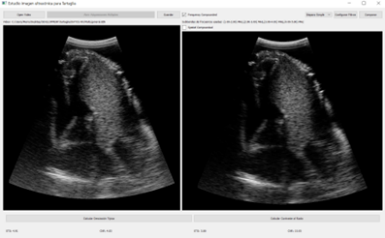

Nuestro reto en TARTAGLIA es el desarrollo de dos ecógrafos orientados a probar el guiado de la sonda cardiaca para la detección optima de las ventanas, concebido especialmente para situaciones de emergencia asistencial. Mediante herramientas interactivas de inteligencia artificial desarrollada por GMV que simplifiquen la realización del examen y la interpretación de las imágenes, se pretende extender la ecografía de cardiaca a un mayor número de profesionales y servicios, desde atención primaria hasta cuidados intensivos. El impacto en la capacidad del sistema sanitario para el manejo de los pacientes con patologías cardiacas sería muy positivo, ya que se trata de una herramienta muy específica para evaluación de la condición críticas en todas las etapas de la enfermedad, incluidos los potenciales problemas crónicos a medio y largo plazo.

- Se Investigará y desarrollaran algoritmos de conformación de haz capaces de operar en tiempo real estricto sobre la plataforma hardware actual. Implementarán técnicas de multi-beamforming, composición espacial y de reducción de speckle, necesarias para obtener imágenes de calidad en ecografía cardíaca.